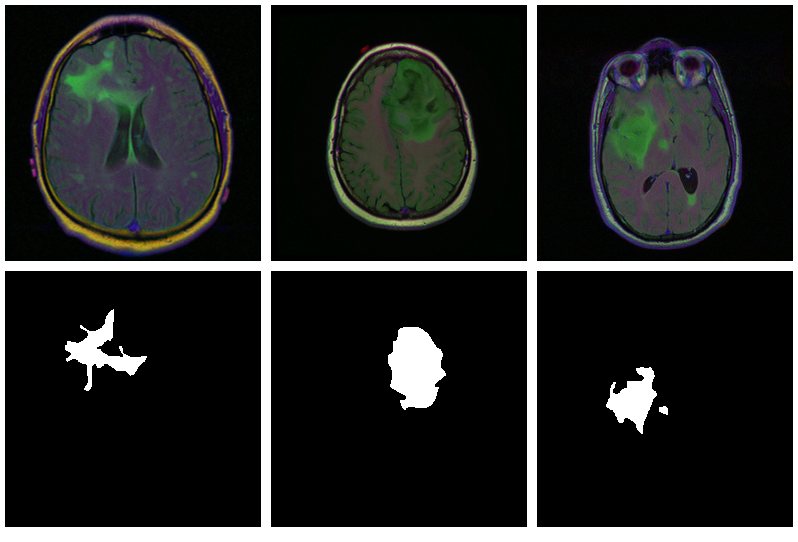

Now, since we don’t have a separate test set, we already know the average out-of-sample metrics; but in the end, what we care about are the generated masks. Let’s view some, displaying ground truth and MRI scans for comparison.

We also print the individual cross entropy and dice losses; relating those to the generated masks might yield useful information for model tuning.

Sample 1, bce: 0.088406, dice: 0.387786}

Sample 2, bce: 0.026839, dice: 0.205724

Sample 3, bce: 0.042575, dice: 0.187884

Sample 4, bce: 0.094989, dice: 0.273895

Sample 5, bce: 0.026839, dice: 0.205724

Sample 6, bce: 0.020917, dice: 0.139484

Sample 7, bce: 0.094989, dice: 0.273895

Sample 8, bce: 2.310956, dice: 0.999824

While far from perfect, most of these masks aren’t that bad – a nice result given the small dataset!